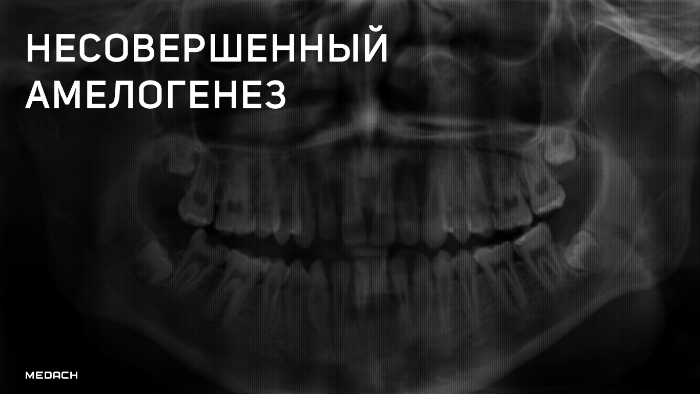

Рентгенограмма при несовершенном амелогенезе

Несовершенный амелогенез

Несовершенный амелогенез (amelogenesis imperfecta) — это тяжёлое наследственное нарушение эмалеобразования, которое выражается в нарушении структуры и минерализации временных и постоянных зубов, изменении их цвета и последующей частичной или полной потерей ткани. НА относится к числу наиболее редких и недостаточно изученных пороков развития твёрдых тканей зубов, имеет различные формы, разные клинические проявления, а также разные типы наследования. Распространённость варьирует от 1:700 до 1:14000 в зависимости от исследуемой популяции.

В норме эмаль имеет высокую рентгеноконтрастность по сравнению с дентином. При гипоматурационной форме НА эмаль и дентин имеют равную рентгеноконтрастность, а при гипоминерализованной форме — рентгеноконтрастность дентина выше. При гипопластической форме на рентгенограмме сразу виден тонкий слой эмали.